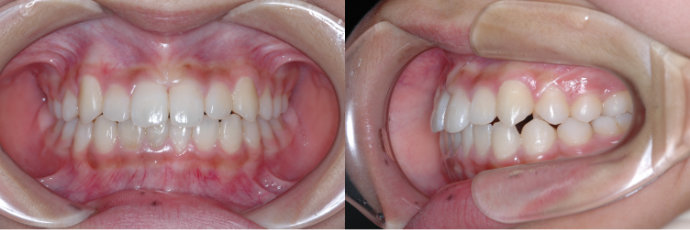

| Case2 |

| 出っ歯 |

| <治療前> |

| <治療後> |

| 主訴 |

上の前歯が出ている |

| 診断名 |

上顎前突 |

| 年齢 |

8歳 |

| 使用装置 |

マルチブラケット装置/ヘッドギア |

| 抜歯部位 |

永久歯の抜歯は無し |

| 治療期間 |

3年6か月 |

| 治療費概算 |

検査・診断料:5万円+税 装置・技術料:25万円+税 来院ごとの処置・管理料:5,000円+税 保定装置料:5万円+税 |

| リスク・副作用 |

特になし |